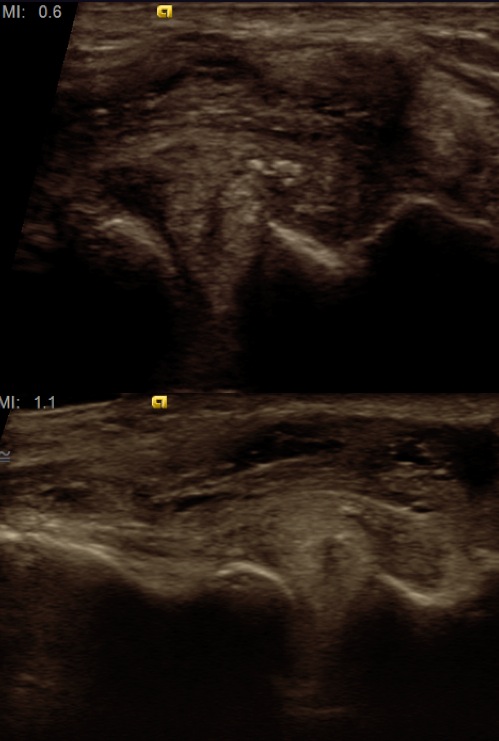

Figure 2 for case horizontal cleavage tear of the lateral meniscus

Figure 2